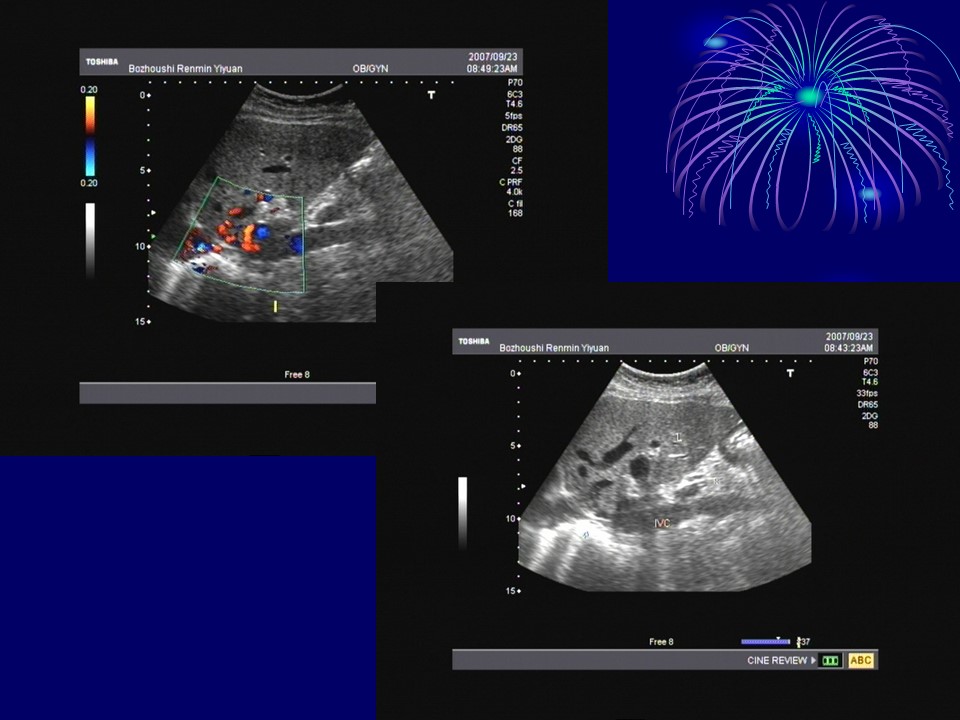

“布加综合征BCS超声诊断PPT” 的相关文章